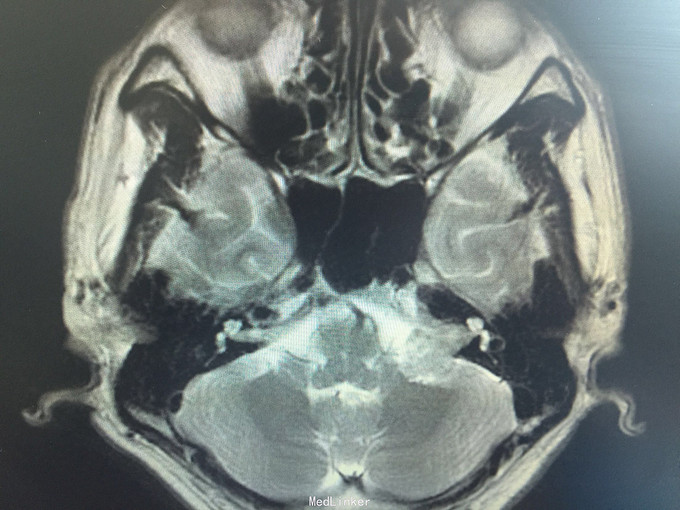

男,52岁,以“左耳鸣、听力下降1年余”入院。 现病史:1年余前看电视时出现左耳鸣、听力下降,左耳听电视声音时听不清,较右侧明显下降,未在意,之后听力下降逐渐至丧失! 既往史:既往高血压、糖尿病病史,长期吸烟病史。 家族史:无特殊!

查体:BP:150/90mmHg,心肺腹未见异常,神清语明,左耳听力丧失,无面瘫,双瞳孔等大正圆,直径约3.0mm,光敏,四肢肌力5级,肌张力正常,巴氏征R-L-。

1.左侧听神经瘤